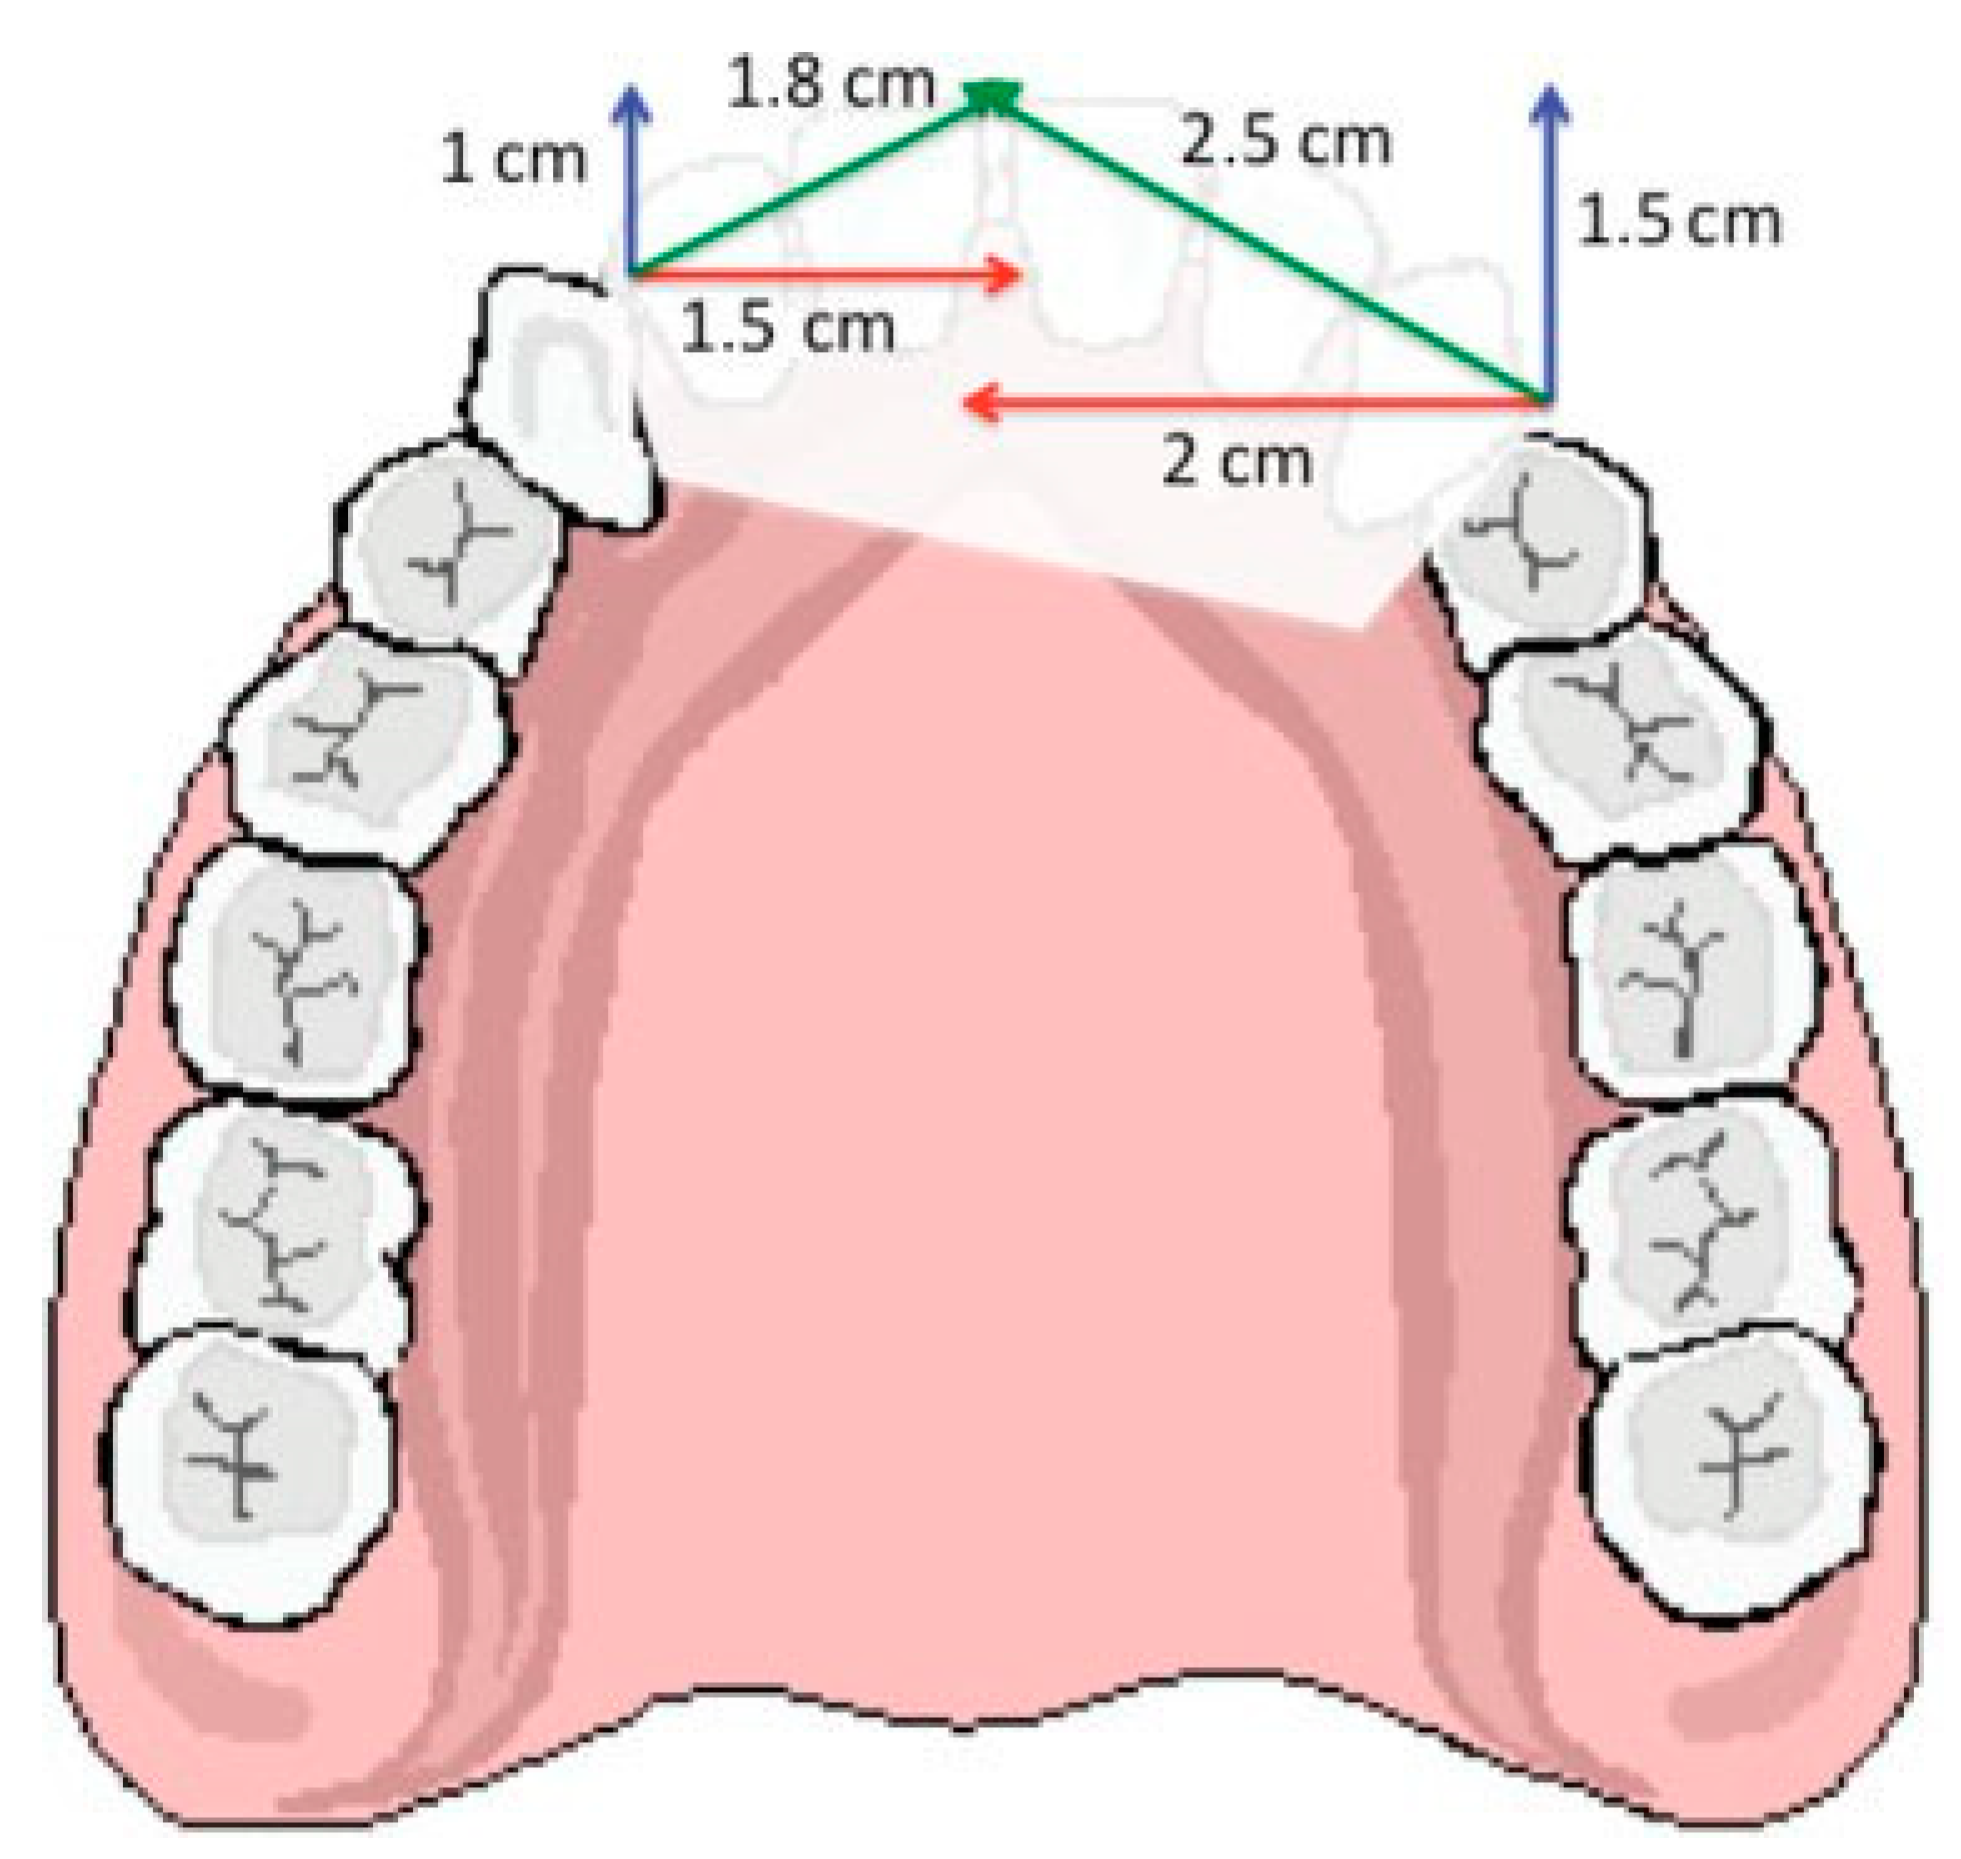

As with other indications for distraction osteogenesis, vector control is important, not only to achieve the closure of the defect but also to obtain the proper anterior projection of the reconstructed maxilla and consequently the dental arch compatibility [12,13]. The final vector or vectors of distraction have three components: the lateromedial, responsible for defect closure; the posteroanterior, responsible for projection of the maxilla; and the vertical component, responsible for dental arch compatibility. For a given defect, if a trifocal distraction is planned with two transport discs and two distractors, the width of the defect measured on the computed tomography (CT) scan, or on the defect itself, should be divided into two and the sum of both lateromedial component vectors would represent the width measure of the defect. Posteroanterior deficiency for each side could be measured on the lateral radiogram or on the defect itself and determines the posteroanterior component vector dimension. The final vector to which the body of the distractor device should be placed parallel is the result of graphic triangulation of these two (Figure 1). The vertical component does not need to be calculated, as the final vector should be parallel to the occlusal plane. The final resultant vector calculated as described should have the direction and length to determine, respectively, the position of the distraction device body and the predicted length and consequently duration of distraction.

Figure 1. A schematic representation of the anterior segmental defect of the maxilla. Red vectors represent the lateromedial component vectors. Blue vectors represent the posteroanterior component vector. Green vectors represent the final resultant vectors obtained by graphic triangulation.